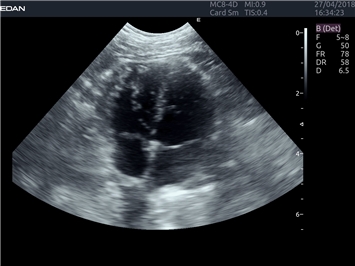

EDAN Acclarix LX4 VET представляет собой профессиональную ультразвуковую систему, специально разработанную для ветеринарных исследований. Сочетание стабильности, высокой производительности и эффективности делает эту систему идеальным выбором для современной ветеринарной практики.

B-режим, Двухмерное сканирование:

Да